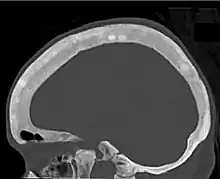

Ground glass density of the skull.[18]

Ground glass density of the skull.[18] CT shows focal areas of osteosclerosis.[18]